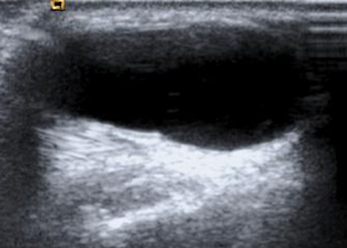

Fig 218 A. Ganglión.

Ecografía sagital. Lesión de consistencia líquida en el dorso de la muñeca, por ganglión.